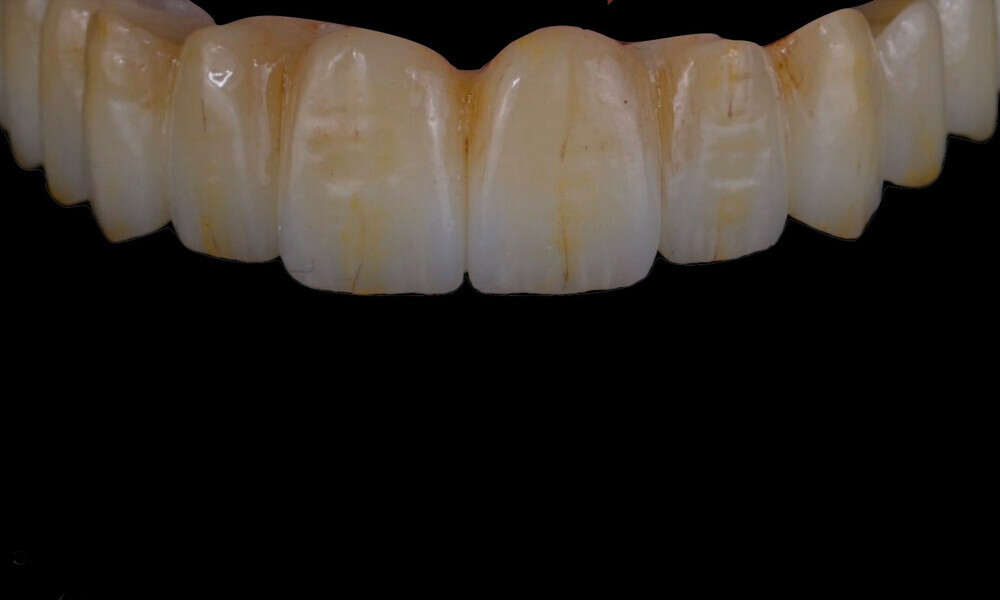

Four months later, we proceeded with the final prosthetic procedure based on clinical and radiographic evidence confirming osseointegration. The case was completed using Straumann RevEX scan bodies for a full monolithic design with a completely digital workflow. First, an intra-oral scan of the opposite arch was taken, followed by an intra-oral scan with the screwed-in temporary abutments. An intra-oral bite scan and an intra-oral scan of the soft tissue with the screw-retained abutments in place were then taken. The reverse scan bodies were attached to the provisional prosthesis, which was scanned extra-orally. Next, the prototype and verification jig were designed, followed by the milling of the prototype and verification jig (Figs. 45 & 46).

During the next visit, the milled prototype and verification jig were tried in, and the design and manufacturing of the final prosthesis were completed (Figs. 47 & 48). The final abutment utilised was Variobase for bridge (Straumann), placed on top of the screw-retained abutments. The material chosen for the final prosthesis was monolithic zirconia (Figs. 49 & 50).

The delivery of the final prosthesis was then performed, and the aesthetics, occlusion and function were verified (Figs. 51–55). The panoramic control radiograph showed that all measurements were within expected ranges (Fig. 56).